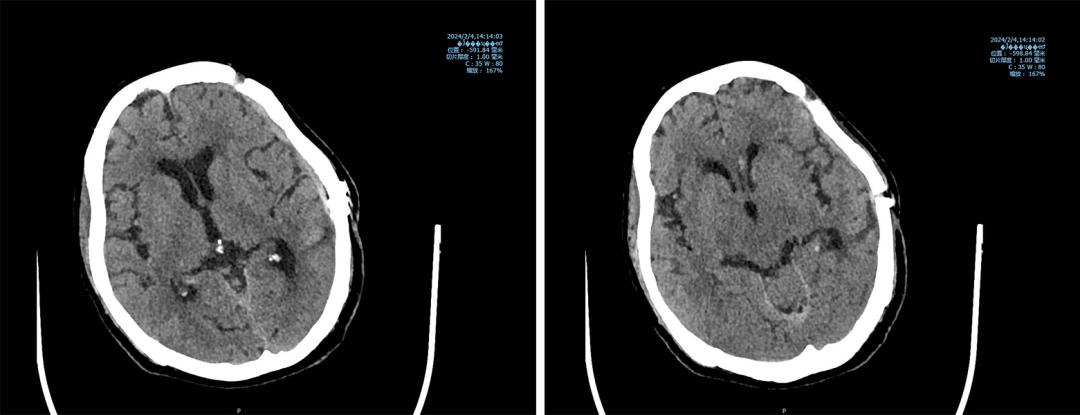

出院前,颅内情况良好,完成自体颅骨修补

终于,在医患双方的共同努力下,老人奇迹般地康复了。她重新站了起来,不仅身体机能逐渐恢复,更重要的是,那份对生活的热爱与向往也如星星之火般重新焕发出光彩。而今日,患者的泪水与家属的笑容交织在一起,这不仅仅是对医生们辛勤付出的肯定与感激,更是对生命奇迹的无限感慨与敬畏。